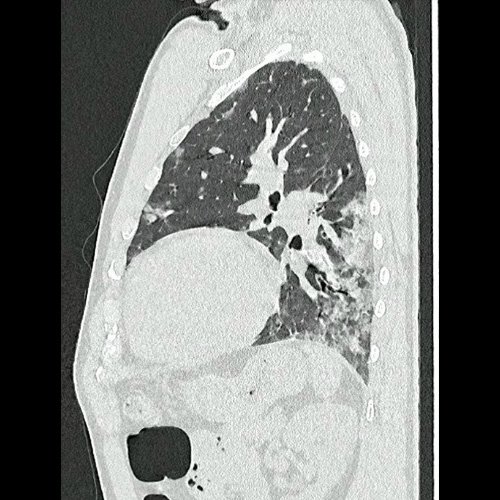

• Tomografía de tórax sin contraste endovenoso (Dia 0):Se observan múltiples áreas de consolidación parenquimatosa con broncograma aéreo y de distribución difusa por ambos pulmones, predominando en los lóbulos inferiores, asociadas a engrosamiento de los septos y rodeadas de tenue vidrio esmerilado. Se identifican estructuras ganglionares lateroaórticas, pretraqueales y subcarinales, ninguna de ellas sin alcanzar rango megálico.

Tomografía de tórax sin contraste endovenosos (Ventana pulmonar- corte sagital)